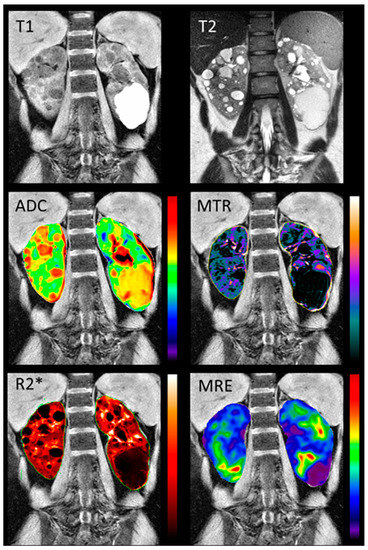

To improve the specificity, and gain the most insight into kidney disease pathophysiology, individual MRI modalities are likely to benefit from their combination in a single acquisition session, through the so-called multiparametric MRI approach, therefore enabling a comprehensive characterization of the kidney tissue and function [104]. Two recent studies have highlighted the potential of averaging volumes obtained from different anatomical MRI sequences, following proper quality control, to mitigate possible TKV measurement bias, and thus improve the TKV reproducibility [105,106]. In addition, there is only one study so far that has used multiparametric renal MRI in ADPKD patients [87]. Comprehensive multi-parametric renal MRI scans, including T1-weighted, T2-weighted, FIESTA, 2D PC-MRI, DWI, MTI, BOLD MRI, and MRE (Figure 5) were acquired in 10 young adults with normal renal function, and 10 early ADPKD patients. The quantitative MRI sequences were found to be reproducible. Moreover, a significant difference between the ADPKD non cystic renal parenchyma and the normal renal tissue was found in the MTI, DWI, BOLD, and MRE biomarkers, suggesting the potential of multiparametric renal MRI in detecting and following renal disease from the earliest disease stages.

Figure 5.

Examples of the multiparametric MRI of the kidney in a representative ADPKD patient. The top row shows structural MRI scans (T1- and T2-weighted). The second and third rows show quantitative maps, overlaid on the T1-weighted scan: the apparent diffusion coefficient ‘ADC’ derived from DWI, the magnetization transfer ratio ‘MTR’ derived from MTI, the apparent transverse relaxation rate ‘R2*’ derived from BOLD, and the tissue stiffness map derived from MRE. The figure was reprinted with permission from Kline, T.L. et al. Quantitative MRI of kidneys in renal disease [87].